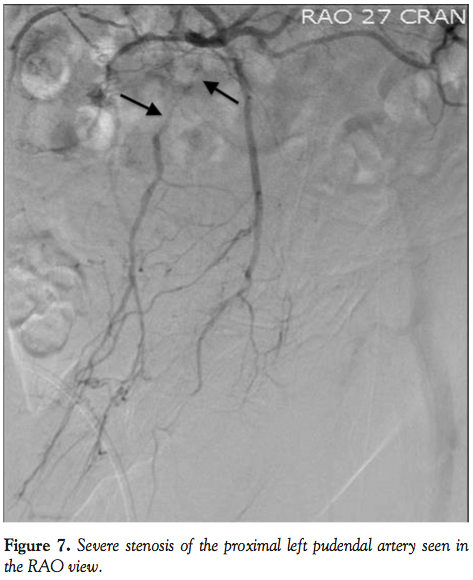

Arterial access was achieved with placement of a 12 cm, 5 Fr sheath in the right common femoral artery. Non-selective digital subtraction angiography was performed with a 5 Fr pigtail catheter in the descending aorta, demonstrating patent internal iliac arteries and obstructive disease of the left pudendal artery. A 5 Fr internal mammary guide catheter was advanced over a 0.035-260 cm, stiff-shaft, angled hydrophilic wire and positioned at the ostium of the left internal iliac artery. Digital subtraction angiography at the flat AP position, 30° RAO, and 30° LAO angulation demonstrated severe disease in the left internal pudendal artery (Figure 7 RAO and Figure 8 AP).

A 0.014˝, 180 cm coronary wire was used to cross the lesion in the left internal pudendal artery. A 2.0 x 20 mm coronary monorail balloon was used to dilate the lesion with serial inflations to 10 atm. Angiography following balloon dilation demonstrated a suboptimal result with dissection of the artery (Figure 9). A 2.5 x 28 mm coronary drug-eluting stent was positioned in the distal aspect of the lesion and deployed at 10 atm. Another 2.5 x 12 mm coronary drug-eluting stent was positioned in the proximal aspect of the lesion, overlapping the